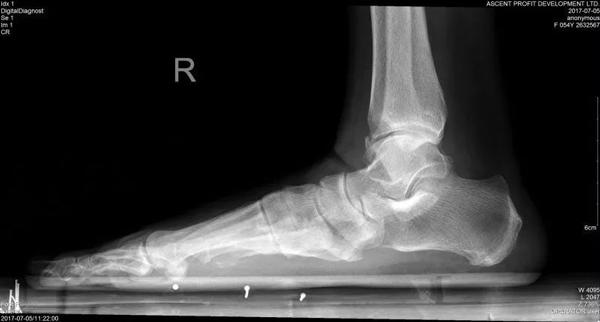

14/06/2018 17:01Thường đeo giày cao gót, người phụ nữ mắc bệnh 'bàn chân bẹt': kiểm tra ngay trước khi quá muộn!

Cô Lí, nay 54 tuổi từng là giáo viên dạy tiếng Anh tại trường trung học. Từ khi còn nhỏ cô đã có một “bàn chân bẹt” – tức là gan bàn chân phẳng lì, không có vết lõm vòng cung như mọi người.

Dù đã tới nhiều bệnh viện để kiểm tra và điều trị nhưng cơn đau của cô Lí vẫn không thuyên giảm, cho tới khi cô gặp được bác sĩ Miêu Húc Đông. Bác sĩ Miêu đã tiến hành kiểm tra bàn chân cô Lí và phát hiện cô bị “hội chứng bàn chân bẹt” vì thường xuyên đứng lâu, đi giày cao gót.

Hội chứng bàn chân bẹt là gì?

Bàn chân bẹt, gan chân phẳng lì là một dạng dị tật phổ biến trên thế giới, gây ảnh hưởng nghiêm trọng đến thần kinh cột sống.

Tất cả trẻ sơ sinh đều có bàn chân không có vòm, hay còn gọi là bàn chân bẹt. Khi trẻ đến độ tuổi từ 2 đến 3, vòm bàn chân được hình thành. Cùng với hệ thống dây chằng, vòm bàn chân giúp cho chúng ta có thể chịu lực, cân bằng, đi đứng nhẹ nhàng, giúp giảm phản lực từ mặt đất dội lên khi chân di chuyển. Thông thường, những ai có hệ thống dây chằng quá lỏng lẻo sẽ dễ bị bàn chân bẹt. Đó là vì các xương ở bàn chân không được cố định tốt.

Bác sĩ Miêu cho biết cứ 100 người thì có khoảng 7 người sẽ bị hội chứng bàn chân bẹt. Để kiểm tra xem liệu bạn có bàn chân khác biệt hay không, hãy dẫm chân vào nước sau đó tìm một mặt phẳng khô ráo và bước chân lên rồi nhìn vào dấu chân.

Dấu chân bình thường sẽ có một vết khuyết ở giữa gan bàn chân, còn nếu bạn có một dấu chân hoàn chỉnh, không có phần cong khuyết vào thì đó là hội chứng bàn chân bẹt. Để biết chính xác hơn, bạn nên đến bệnh viện kiểm tra.